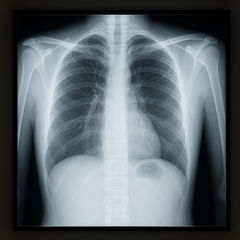

Поэтому вопрос, влияет ли вейп на флюрографию, корректнее рассматривать как анализ косвенных последствий. Флюорография показывает воспаление, инфильтрацию, расширение корней или участки затемнений, но все эти признаки неспецифичны и встречаются при самых разных состояниях — от аллергии до перенесённой инфекции. При лёгком или эпизодическом использовании электронных сигарет снимок может остаться без изменений.

Именно поэтому формулировка «можно ли на флюорографии увидеть, что человек парит электронные сигареты» требует пояснения: увидеть само парение невозможно, но увидеть последствия раздражения дыхательных путей — в отдельных случаях да. Особенно если сочетать вейп с сигаретами или иметь хронические заболевания дыхательной системы.

Врач всегда оценивает общую картину: прозрачность лёгочных полей, состояние сосудистого рисунка, тени корней, наличие уплотнений или участков перегрузки. Эти признаки могут усиливаться у активных курильщиков, но редко бывают специфическими именно для пользователей электроннок.